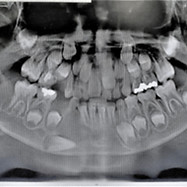

CIRUGÍA MAXILOFACIAL

Cirugía Ortognática

Implantes dentales